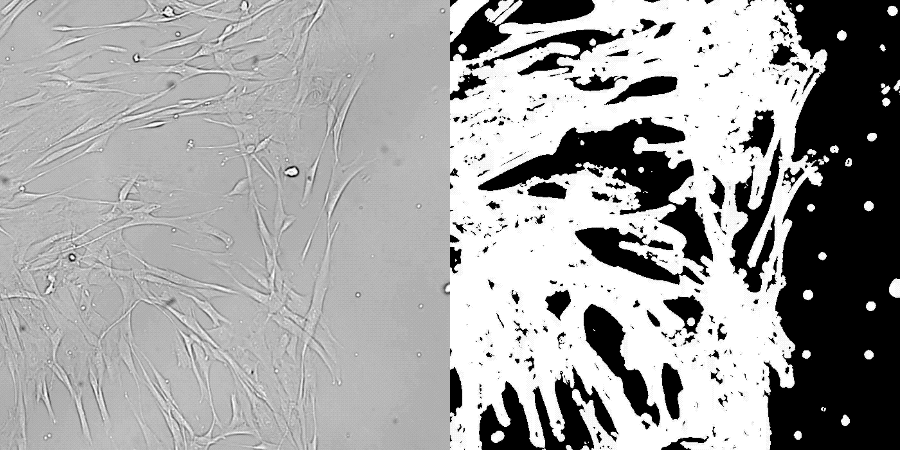

此次研究对象是人类皮肤中的成纤维细胞,这种细胞负责分泌胶原蛋白,在伤口愈合中也有重要作用。

具体方法,先给衰老的成纤维细胞转入山中伸弥发现的4种转录因子,10-17天左右进入成熟期后,再把这些因子移除,让细胞恢复正常状态。

在中间阶段,成纤维细胞的形态和基因表达水平发生变化,去除后再次回到成纤维细胞状态。

一通操作下来,使用表观遗传时钟基因转录物读数两种方法测量,重编程后的细胞大致与年轻了30岁的细胞特征匹配。

在体外伤口愈合实验中,也观察到重编程细胞恢复了活力,能分泌更多胶原蛋白,迁移到伤口的速度也加快。

在后续对比试验中,研究人员发现让转录因子表达13天是最佳平衡点。